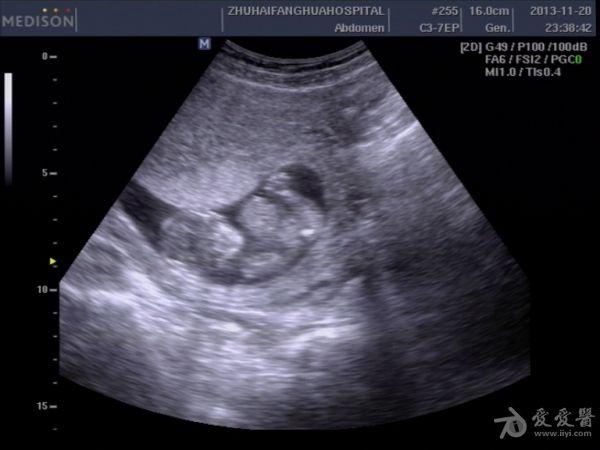

13周孕,24岁,初孕 因腹痛急诊***检查,是当天早上3点钟,医生提的黑白超,学生胆挺大的,超声图像如下:

学生直接诊断胎儿内脏外翻,上班后复查图像觉得问题不大,但还是被学生的胆大吓了一跳。这孩子连孕妇的联系方式都没留,人就放走了,今天终于联系上了孕妇,结果在市产院做的引产,结果同上。学生对我说,本来想诊断脐膨出的,觉得不像,还是像内脏外翻多些,大家说说,这孩子是该批评呢,还是该鼓励。我都有点哭笑不得了。